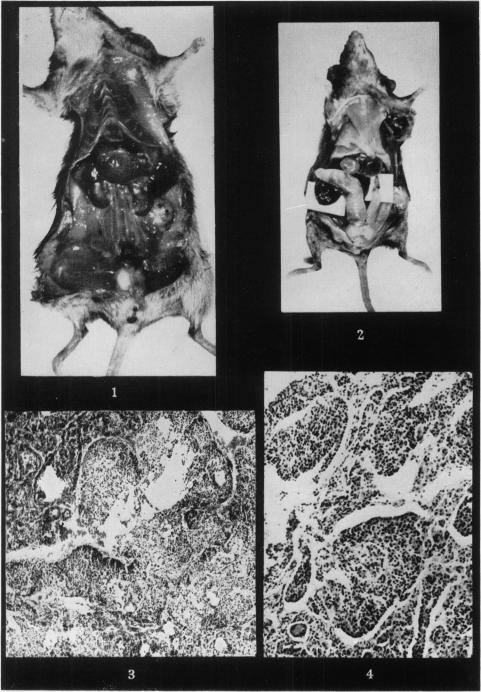

HOWELL J S, MARCHANT J, ORR J W

Br J Cancer. 1954 Dec;8(4):635-46. doi: 10.1038/bjc.1954.69.